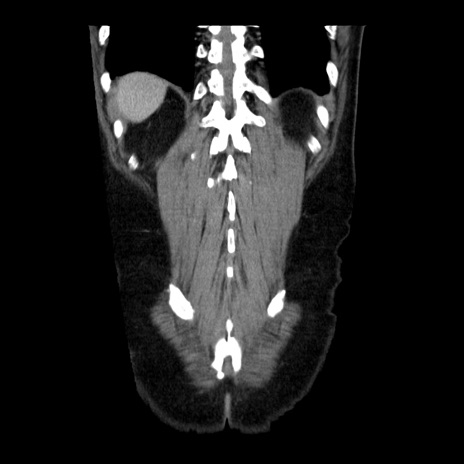

症例29(冠状断像)

【症例】40歳代男性

【現病歴】2日前から胃痛あり。徐々に周期的な激痛に変化した。本日になっても激痛があるため受診。

【身体所見】意識清明、BT 38-39℃台あり、腹部:膨満、やや硬、右下腹部に圧痛あり。

【データ】WBC 8500、CRP 23.26